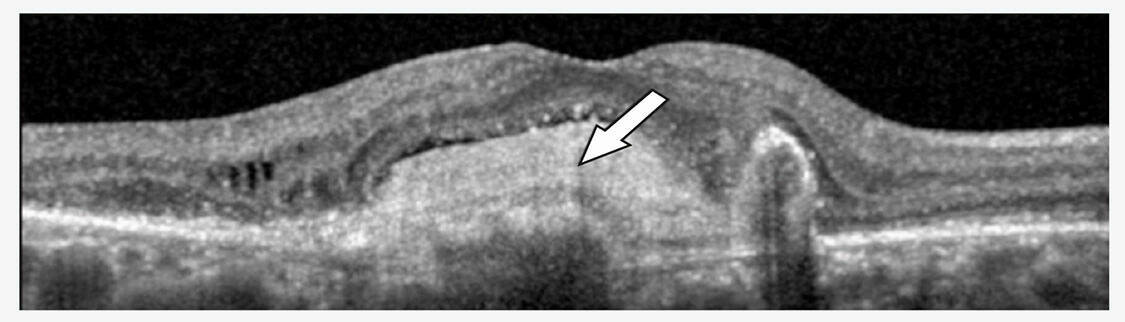

Figure 3. Imagerie multimodale d’une patiente de 34 ans atteinte de PIC. Le panneau (A) montre une photographie en couleur du fond d’œil d’un œil à aspect myopique, présentant des zones d’atrophie en plaques et de multiples lésions de PIC. (B) L’angiographie à la fluorescéine révèle plusieurs foyers hyperfluorescents au pôle postérieur. Le panneau (C) montre une coupe OCT à travers ces zones : en position sous-fovéolaire (pointe de flèche), on observe une lésion active caractérisée par un dédoublement du complexe membrane de Bruch–EPR, une rupture de la membrane de Bruch, une hypertransmission choroïdienne et un épaississement choroïdien ; à l’inverse, une lésion inactive adjacente (étoile) se caractérise uniquement par une interruption du complexe membrane de Bruch–EPR avec hypertransmission choroïdienne. Le panneau (D) montre une angiographie au vert d’indocyanine en phase tardive, avec une ligne hypofluorescente ramifiée compatible avec des lacquer cracks (étoile). Le panneau (E) montre l’autofluorescence du fond d’œil au niveau du pôle postérieur, où les lésions actives apparaissent comme des zones de légère hyperautofluorescence (pointe de flèche), tandis que la cicatrice atrophique centrale apparaît hypoautofluorescente.